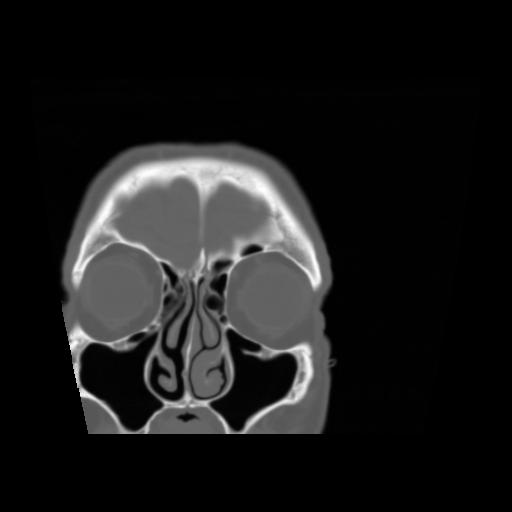

5 CEREBRO,,Coronal,3.000,CEREBRO,Coronal,